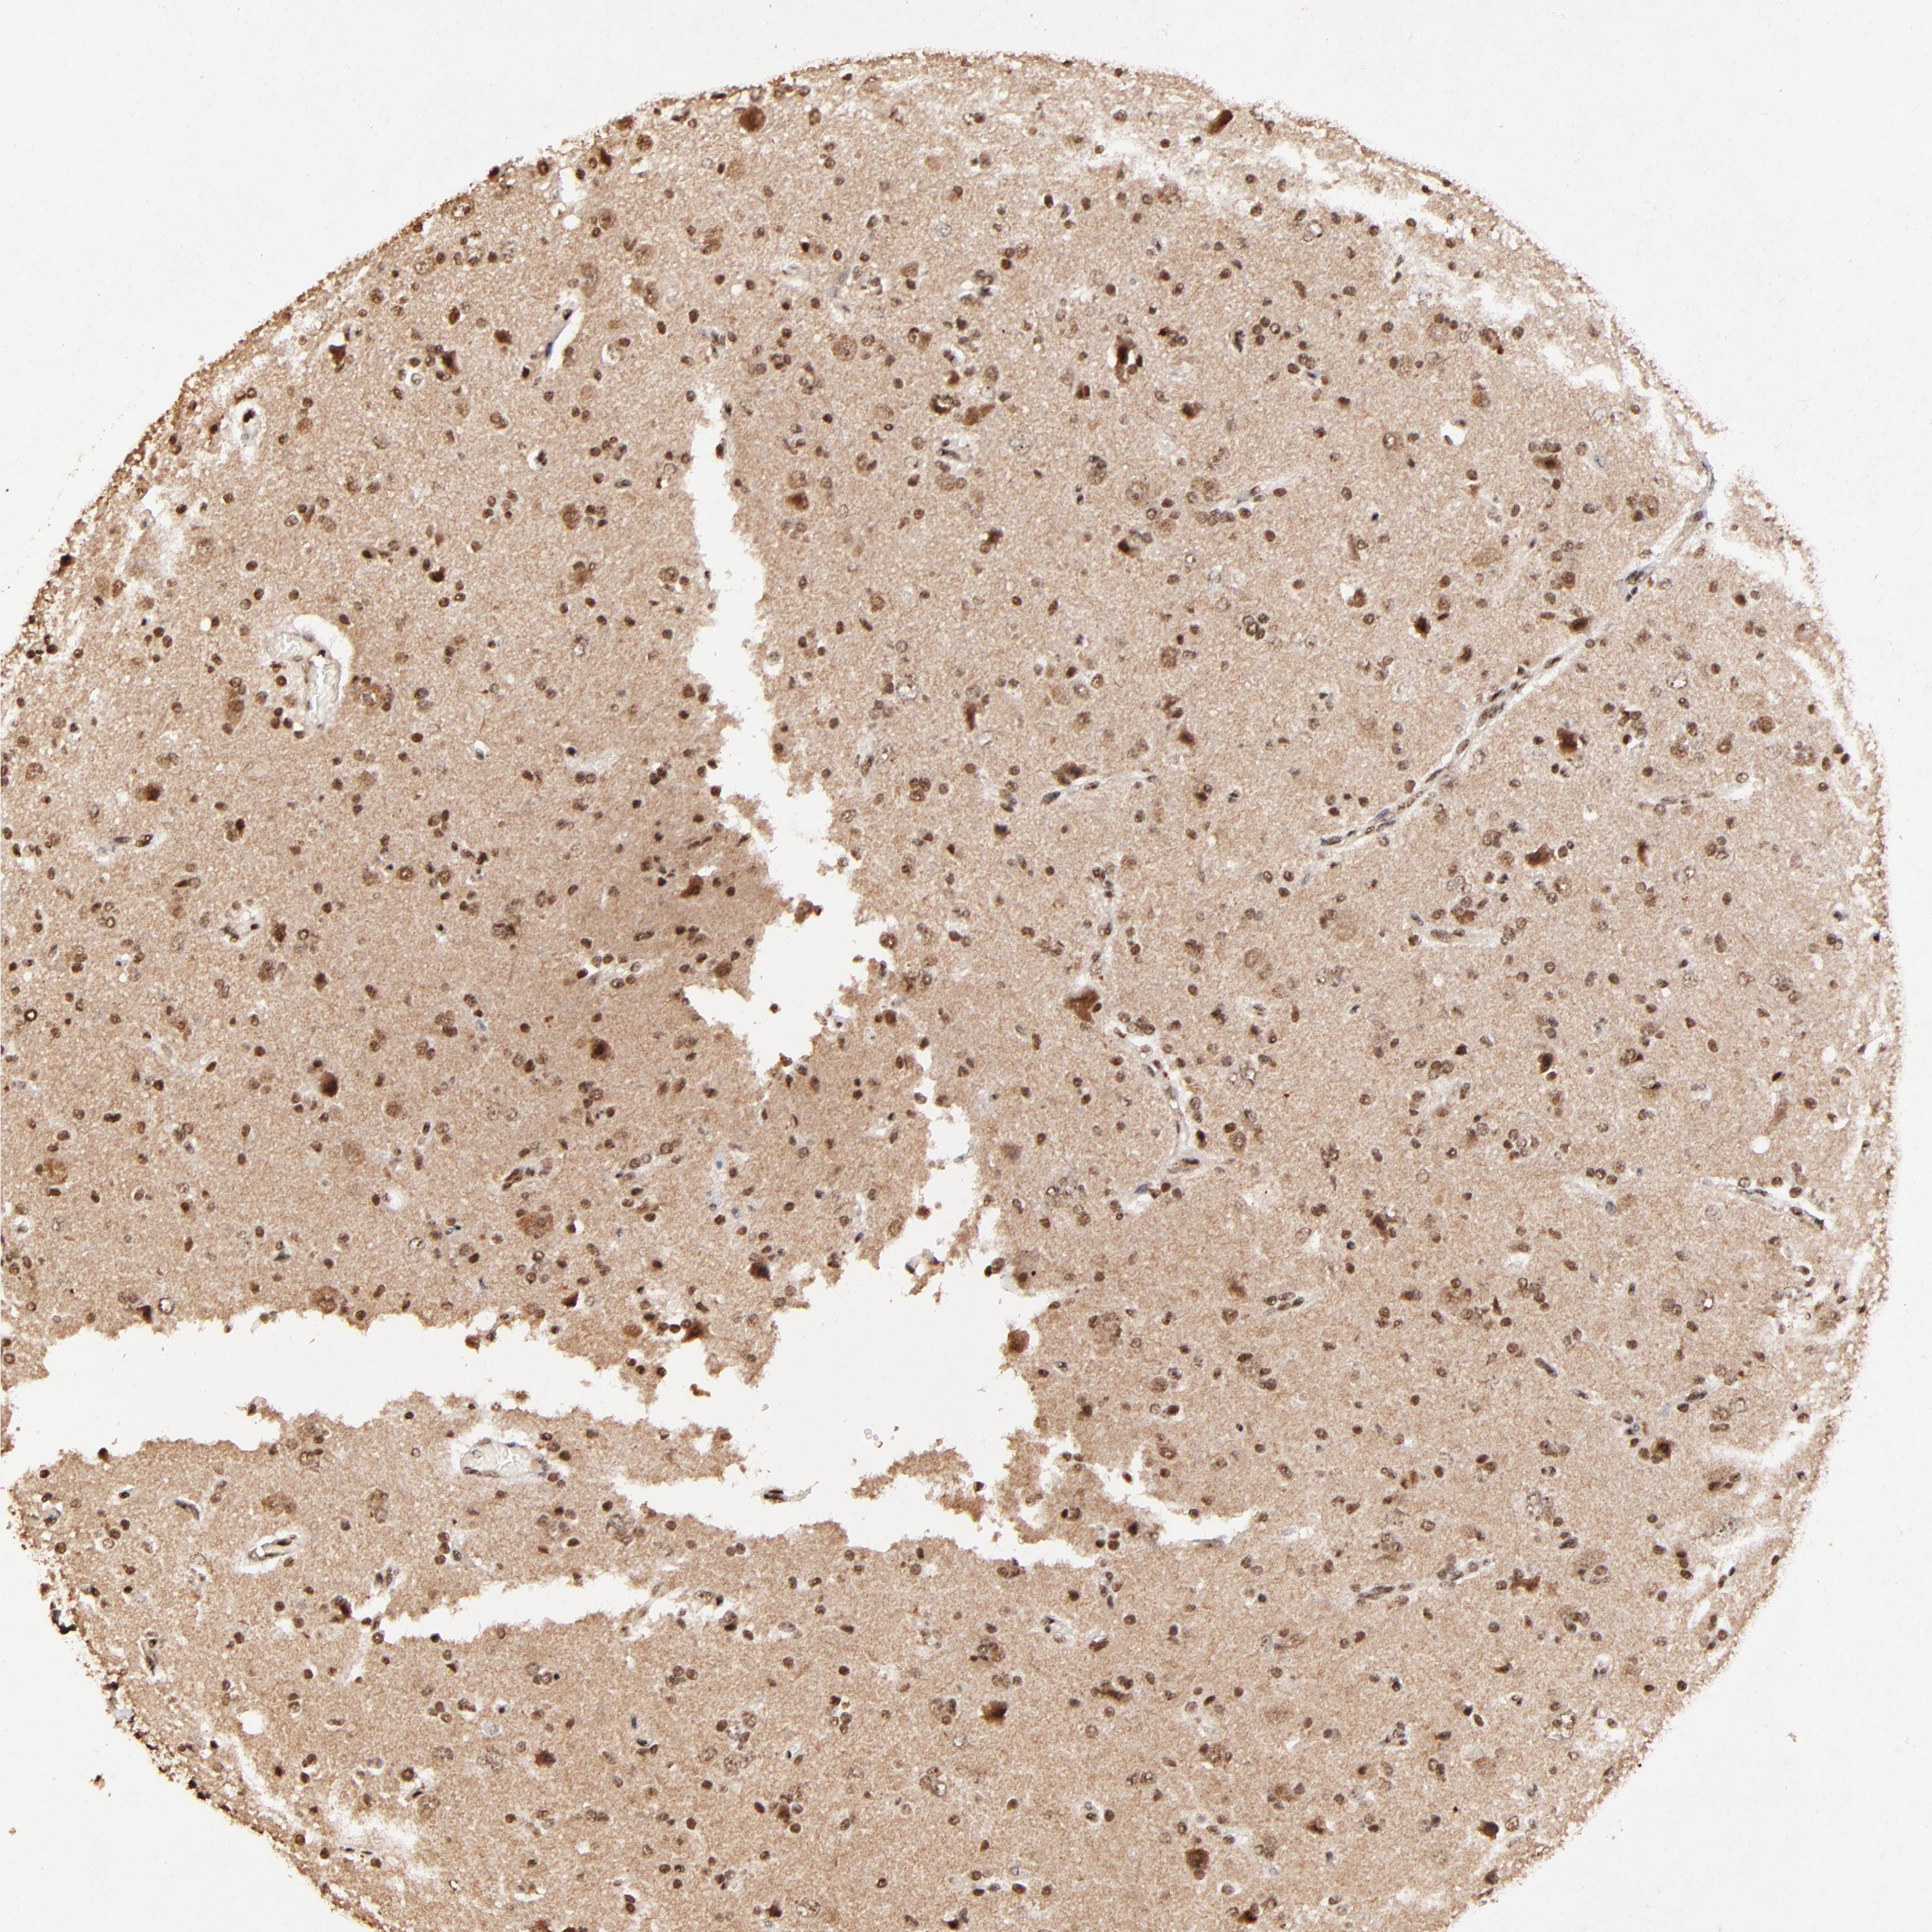

GLIOMA - Protein expressioni

A mouse-over function shows sample information and annotation data. Click on an image to view it in a full screen mode. Samples can be filtered based on level of antibody staining by selecting one or several of the following categories: high, medium, low and not detected. The assay and annotation is described here.

Note that samples used for immunohistochemistry by the Human Protein Atlas do not correspond to samples in the TCGA dataset.

Antibody stainingi

Antibody staining in the annotated cell types in the current human tissue is reported as not detected, low, medium, or high, based on conventional immunohistochemistry profiling in selected tissues. This score is based on the combination of the staining intensity and fraction of stained cells.

Each image is clickable and will lead to virtual microscopy that enables deeper exploration of all samples and also displays staining intensity scores, fraction scores and subcellular localization as well as patient and tissue information for each sample.

Antibody HPA003184

Antibody HPA003185

Staining

High

Medium

Low

Not detected

Intensity

Strong

Moderate

Weak

Negative

Quantity

>75%

75%-25%

<25%

None

Location

Nuclear

Cytoplasmic/membranous

Cytoplasmic/membranous,nuclear

Glioma, malignant, High grade

Glioma, malignant, Low grade

Glioma, malignant, NOS